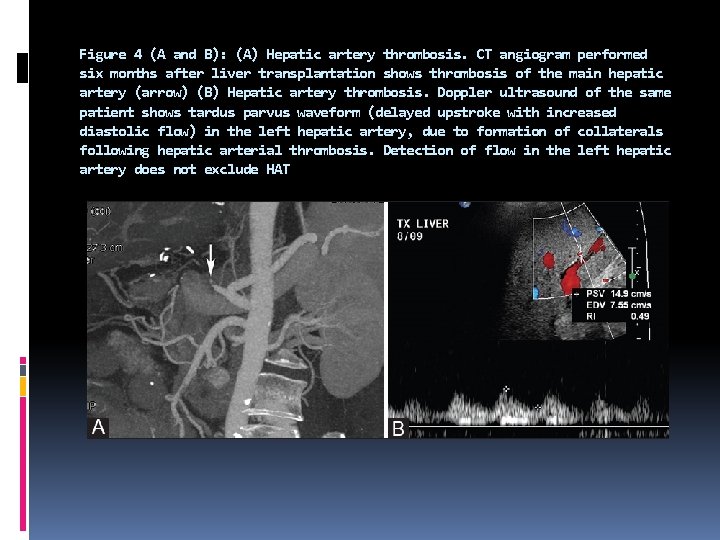

HAT is the most common and devastating complication after liver transplantation, which results in high mortality. Early HAT occurs in the first few weeks and presents with rapid clinical deterioration. Thrombosis occurring after the first month has a more insidious clinical course. HAT requires re-transplantation in majority of the cases. Surgical revascularization may be attempted when the diagnosis is established early in the postoperative course.

Ultrasound is diagnostic in 92% of cases of HAT. On Doppler ultrasound, HAT is diagnosed by the absence of flow in the hepatic arteries. As the allograft edema in the postoperative period can make visualization of the hepatic arteries difficult, it is important to ensure that the gain settings are optimized and a thorough search for hepatic arteries is performed to prevent a false positive diagnosis. A high resistance waveform (RI = 1) may be obtained in the hepatic artery if it is sampled proximal to the site of the thrombosis. On account of the catastrophic nature of this complication, computed tomography (CT) or digital subtraction angiography (DSA) angiography is usually performed to confirm the diagnosis.

Hepatic arterial collaterals can develop after HAT, particularly in the late cases. These collaterals can cause tardus parvus waveforms in the right and left hepatic arteries. Demonstration of such waveforms in the downstream hepatic arteries must not be considered evidence of patency of the more proximal hepatic artery. The tardus parvus waveform does not exclude HAT, but rather indicates the presence of either upstream stenosis or thrombosis.

Figure 4 (A and B): (A) Hepatic artery thrombosis. CT angiogram performed six months after liver transplantation shows thrombosis of the main hepatic artery (arrow) (B) Hepatic artery thrombosis. Doppler ultrasound of the same patient shows tardus parvus waveform (delayed upstroke with increased diastolic flow) in the left hepatic artery, due to formation of collaterals following hepatic arterial thrombosis. Detection of flow in the left hepatic artery does not exclude HAT